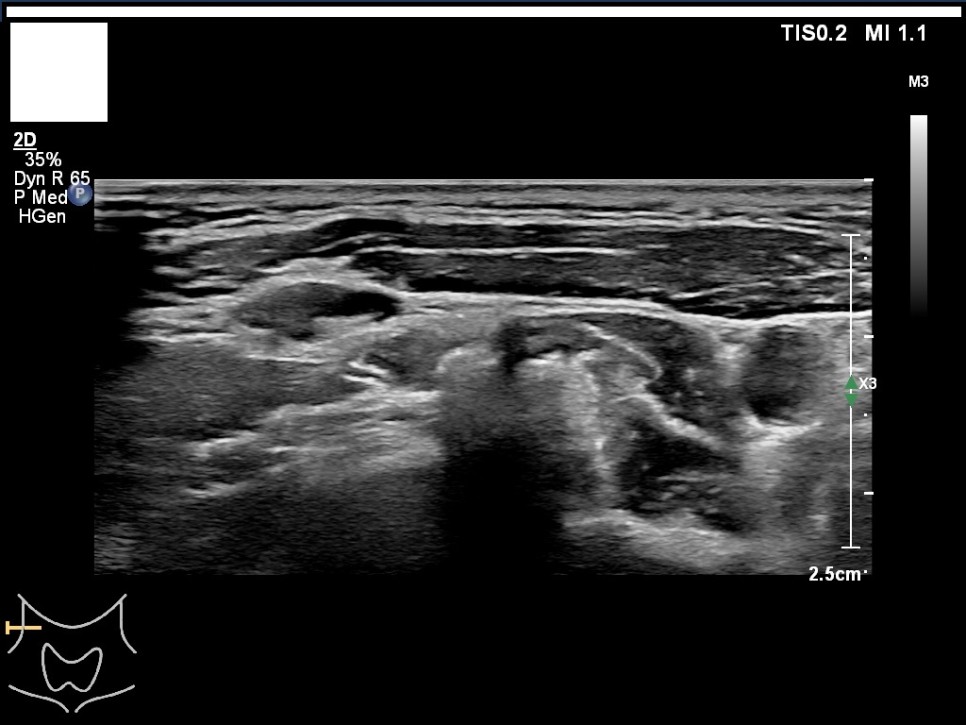

갑상선, 부갑상선 초음파 검사 급여 기준 1. 표준 영상의 범위 모든 영상에는 경부의 해부학적 위치(모식도나 문자)를 표기하여야 한다.

A) 병변이 없는 경우: 우엽 중부 가로 스캔, 우엽 중앙부 세로 스캔, 협부 가로 스캔, 좌엽 중부 가로 스캔, 좌엽 중앙부 세로 스캔, 우경부 림프절, 좌경부 림프절 나) 병변이 있는 경우: 병변이 없는 경우의 표준 영상과 함께 병변 부위에서 2개의 수직 관계 단면 영상(횡단/종단) 및 병변의 크기가 측정된 경우: 병변이 없는 경우의 표준 영상

좌우 이하 선 악하선 가로 스캔 1, 2 / 좌경부 림프절 level 1-4

좌측 경부 림프절 / 중심 경부 림프절 / 협부 옆 스캔 2. 판독 소견서가) 등록 번호, 성명, 생년월일 또는 연령, 성별, 검사명, 검사 일시, 판독 일시, 검사와 판독한 의사(면허 번호), 의료기관명, 검사 소견 및 결론 나) 검사 소견에는 갑상선 에코, 병변의 유무를 기술하여야 한다. 결절이 있을 경우 위치, 최대지름, 주요 소견, K-TIRADS의 내용을 기술하여야 하며, 암으로 진단된 결절을 추적할 경우 위치, 3방향 직경, 주요 소견, 전 검사와 변화 여부, 경부 림프절의 평가 및 이상 소견 여부를 기술하여야 하며, 경부 림프절에 이상이 있을 경우 위치, 크기, 주요 소견을 기술하여야 한다. 결절이 여러 개 있을 경우 암 위험도에 따라 선택적으로 기술할 수 있다. 또 소아 등에서의 환자의 협력도 음창 등이 좋지 않아 표준 영상 획득에 제한이 있는 경우 추가 기술해야 한다.